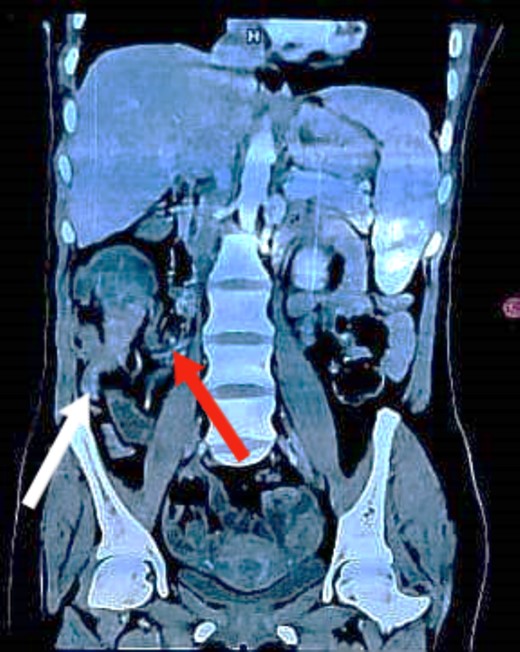

Coronal CT image demonstrating the lesion with the terminal ileum mesentery inside the cecum. The white arrow indicates the inflamed appendix. The red arrow indicates the terminal ileum and its mesentery entering the cecum.

Colonoscopy revealed a malignant-looking mass, the mass appeared irregular, circumferential, fungating and was easily bleeding. It almost occluded the lumen, which correlated with the patient’s symptoms of chronic intermittent intestinal obstruction. The histopathology report indicated invasive moderately differentiated adenocarcinoma. An abdominal CT was conducted and reported a 7 × 5 cm2 soft tissue mass in the ascending colon, highly suspicious for colon cancer, with features of intussusception but no evidence of metastatic disease (Figs 1 and 2). Axial and coronal CT demonstrate the lesion and the intussuscepted bowel].